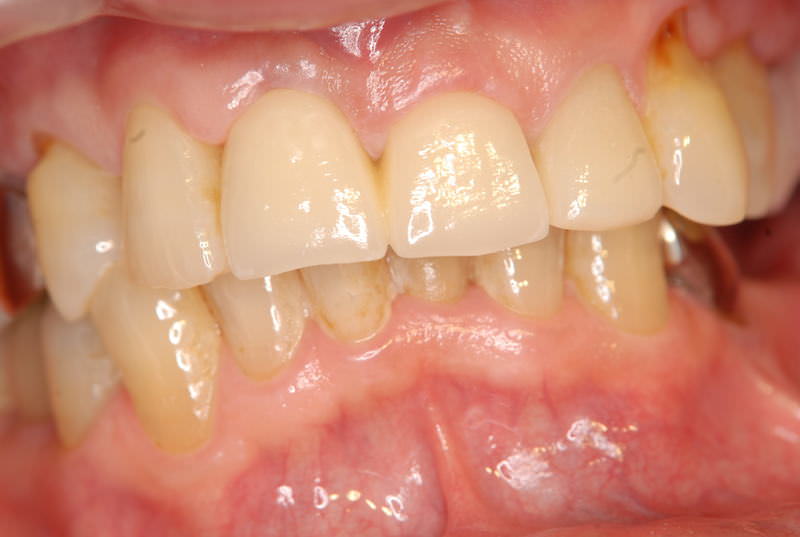

症例140代 男性 主訴 奥歯に歯を入れたい、しっかり噛みたい

治療前

治療後(5年経過)

主訴 奥歯がない為、食事が不自由である。入れ歯は煩わしいので、固定制のインプラントにして欲しいと訴え来院。口腔内全体で6本のインプラントを埋入。仮歯にて神経筋機構、顎関節のバランスを整え、リハビリを経て、約5ヶ月後にジルコニアを装着。

リスクとしては、外科的侵襲がある。デメリットは、保険外診療の為、経済的負担がある。

費用 316万(税込) (オペ・仮歯・最終補綴物まで含む)